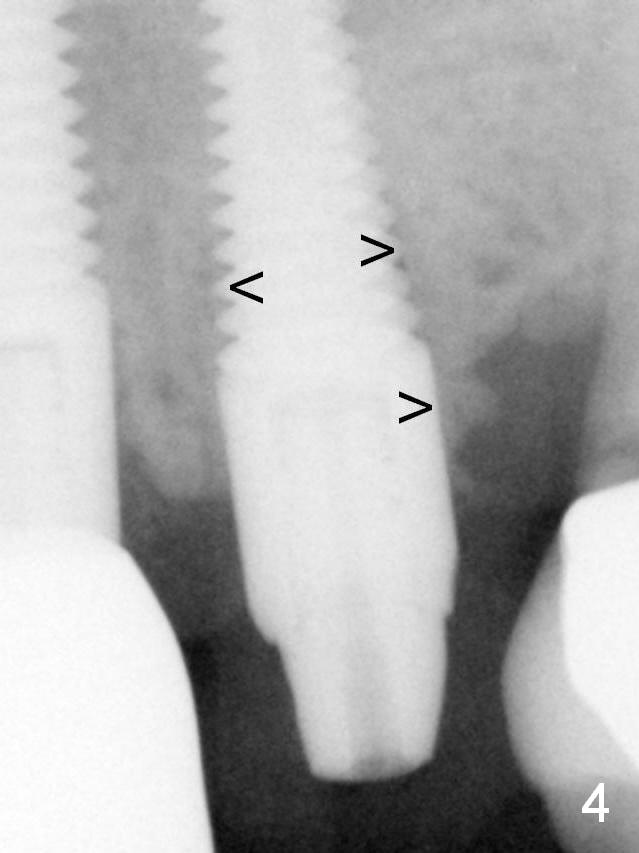

Bone density in the mesial and distal sockets increases after bone graft (Fig.4: arrowheads).